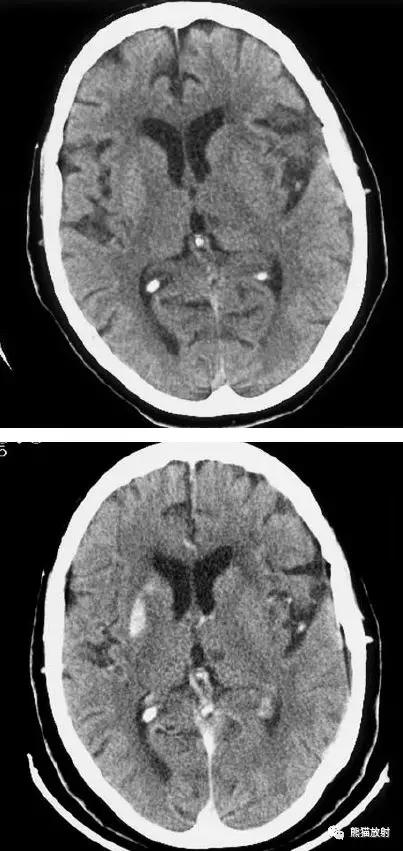

右侧豆状核梗死灶(发病后15d),明显均匀强化。另左侧丘脑见腔隙性梗死灶。

左侧大脑中动脉区域大面积梗死,明显不均质强化。

右侧大脑中动脉区域脑梗死,脑回样强化。

左侧额叶脑梗死(发病后12d),由于模糊效应平扫显示不清,增强扫描脑回样强化。

右侧基底节区脑梗死,增强后病灶看上去有所缩小。